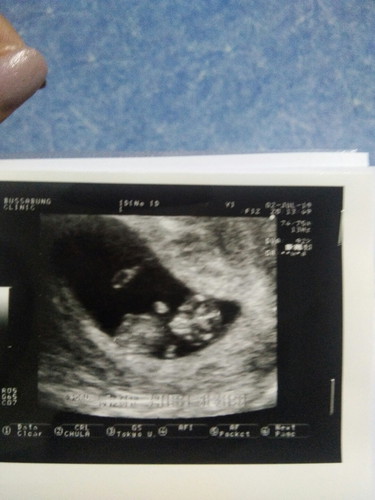

ขอถามหน่อยจ้าเราไปฝากครรภ์มาวันที่2 ก.ค แต่ ปจด. เราขาด11 เม.ย คุยหมอก็คำนวณกำหนดคลอดตอนแรก18 ม.ค แต่พอไปซาวว์ดูและวัดขนาดตัวน้องคุณหมอบอกน้องพึ่งจะได ้9 สัปดาห์ กำหนนคลอดให้เราใหม่คือ1 ก.พ 2563 คุณหมอนัดเรา16 ก.คไปอีกรอบ แล้ววัดขนาดของมดลูกบอกว่าเอาตามที่เราบอกว่า ปจด. เราขาด แต่กำหนดคลอดเราก็ยังเป็น 1 ก.พ 2563 เหมือนเดิมคือเราอยากจะทราบว่าตอนนี้เรากี่เดือนแล้วค่ะ รูปตอนไปฝากครรภ์ค่ะ ท้องแรกค่ะ ขอความคิดเห็นผู้รู้หน่อยจ้า